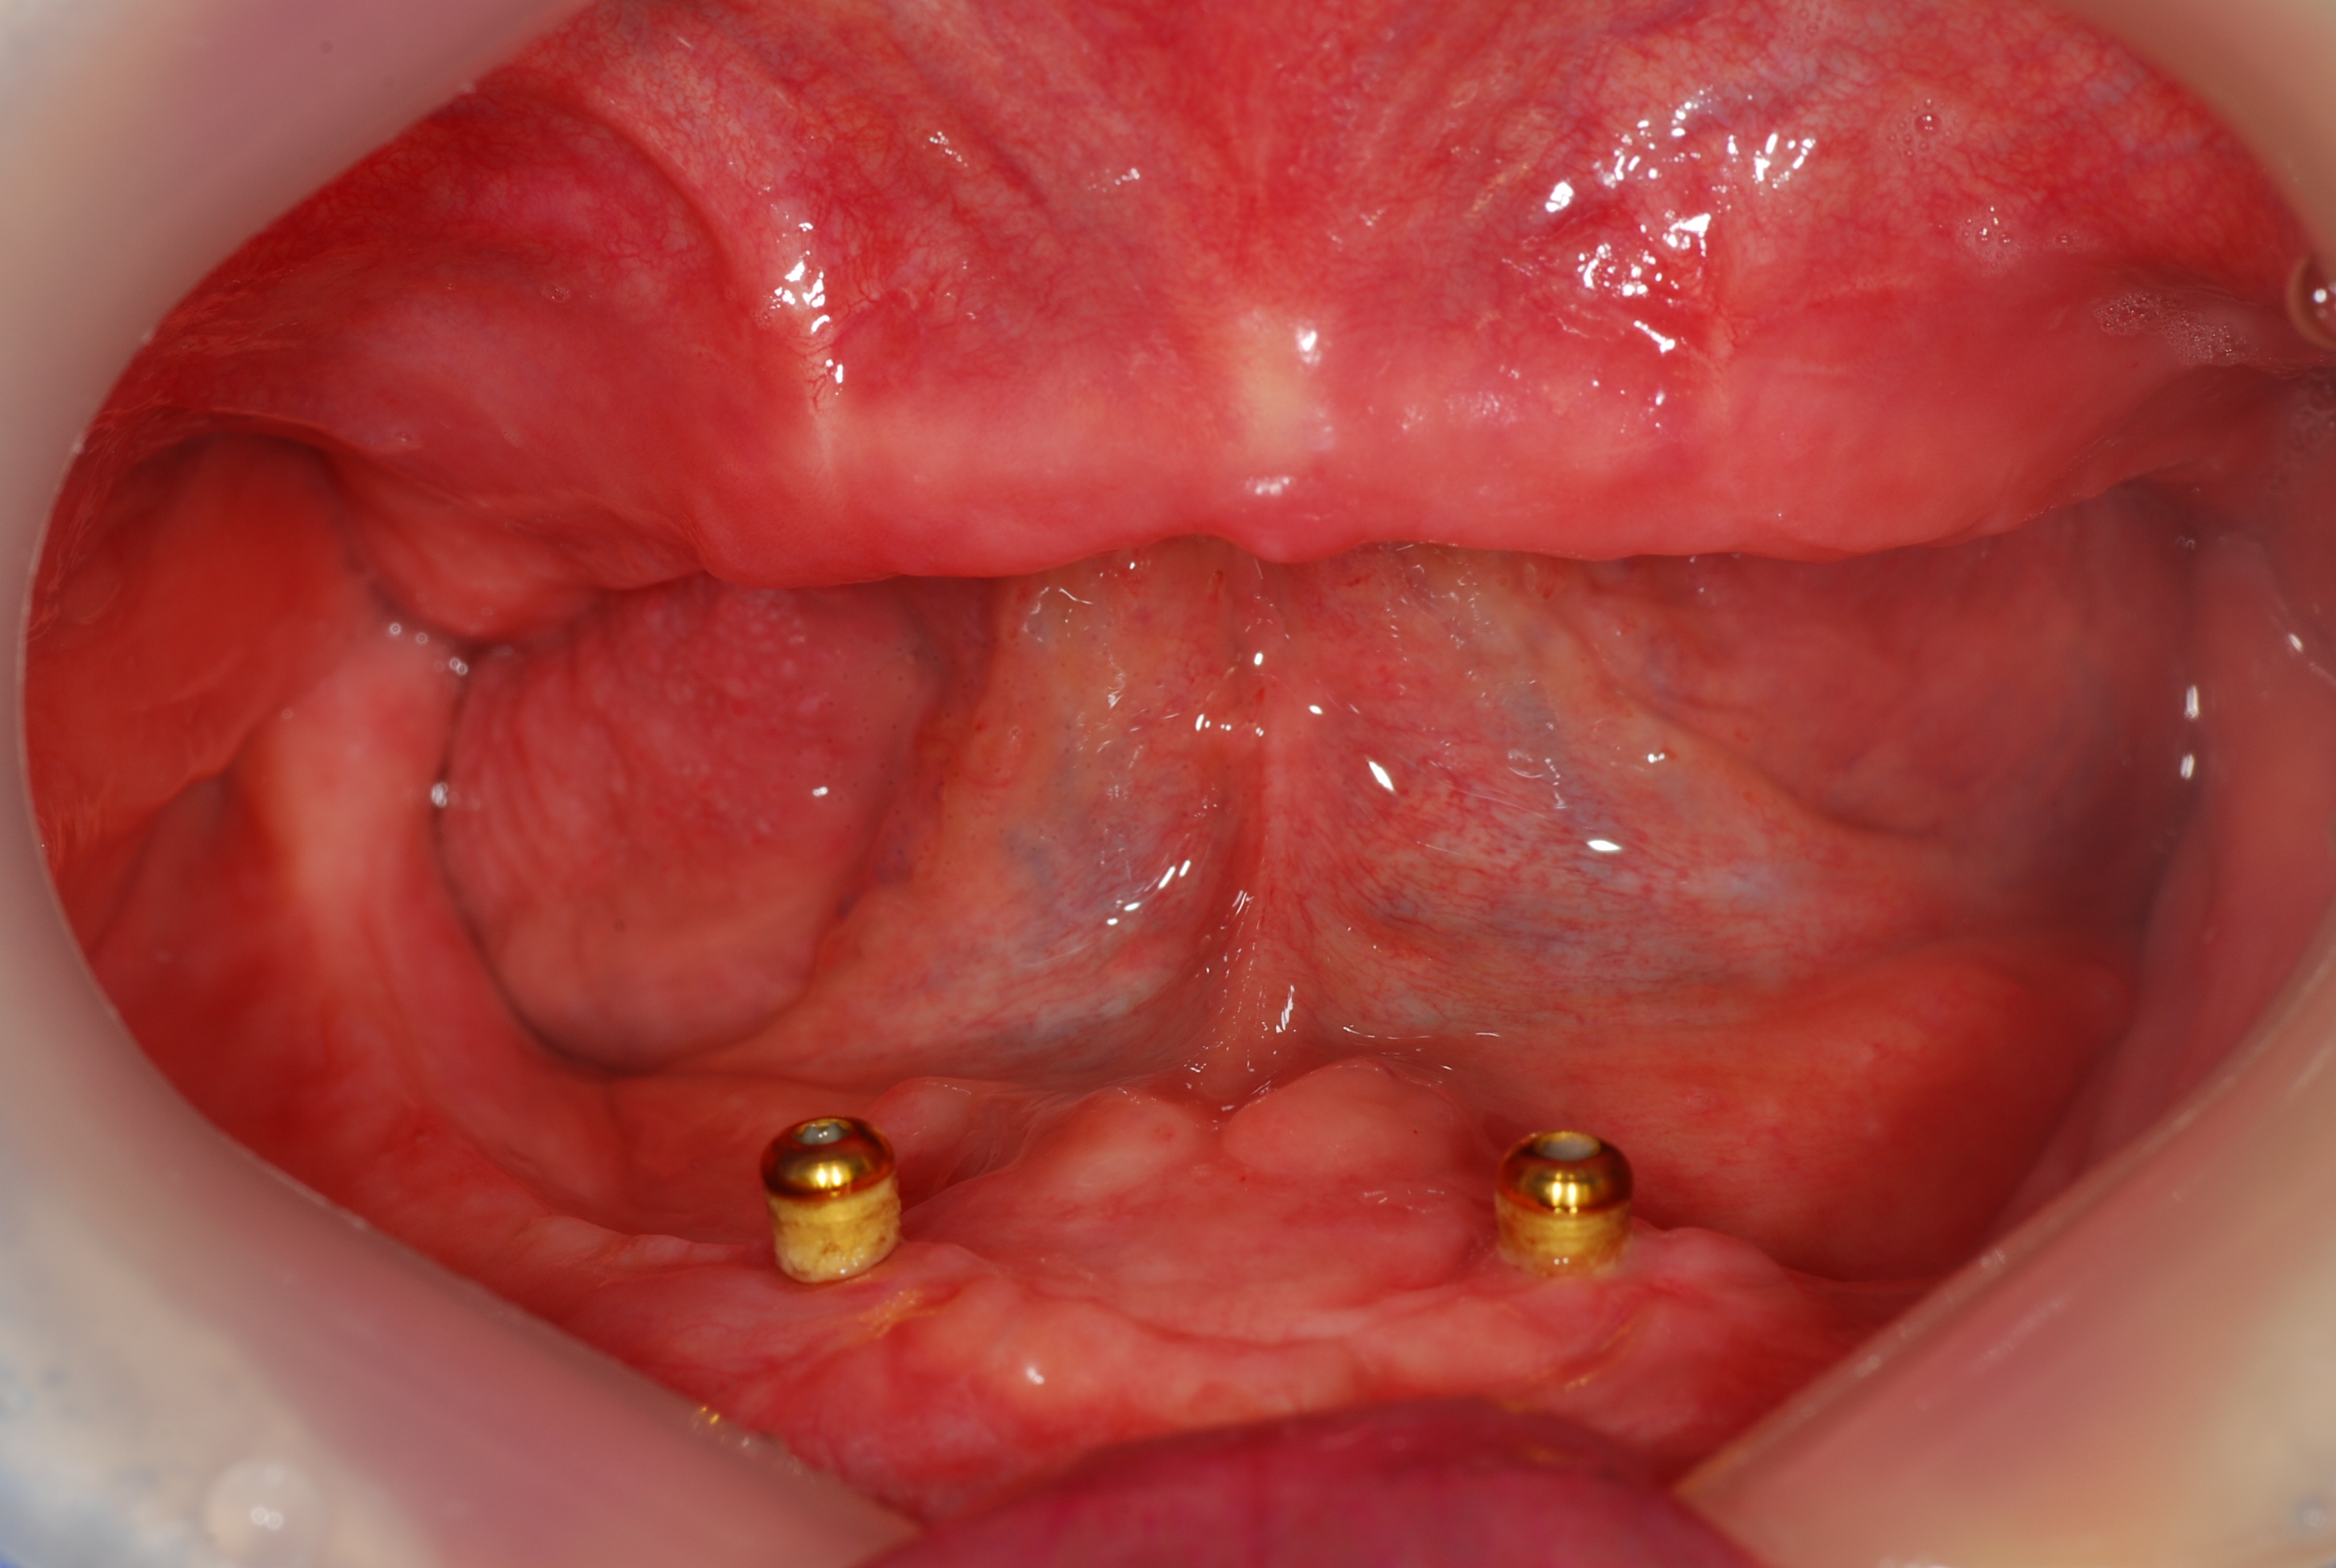

Full-implant (upper jaw), Over denture (lower jaw), Sinus-lifting

66 y.o, Indonesia, Surabaya

Operating dentist:Roh Hyun Ki